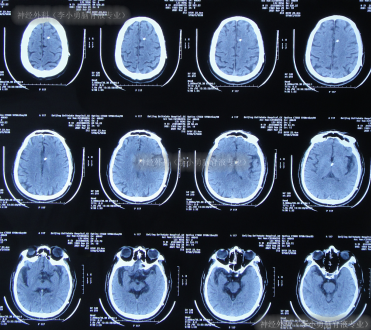

住院1周左右时间,期间曾3次查头颅CT(图-2)示脑室稍有扩张,但头晕症状慢慢消失,行走不稳缓解,认为“病情变好”出院。

图-2:3次查头颅CT